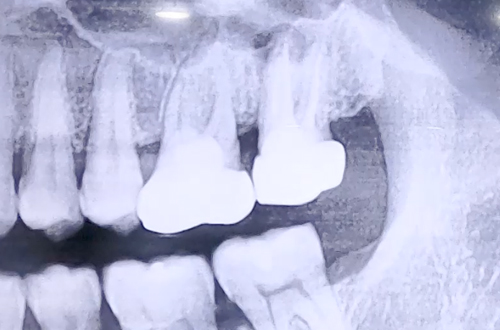

BEFORE

왼쪽 위 큰 어금니의 통증을 호소하며 내원해 주셨던 환자분이신데, 환자분 본인도 아마도 이를 빼야 할것 같다고 말씀하실 정도의 상태이셨습니다.

가능한 자연치아를 쭉 가져가는 것이 좋으므로 자세히 검사해 보고 그 다음에 이를 빼자고 하여 엑스레이를 찍어보니 염증이 발견되었습니다.

신경치료가 되어 있던 치아이므로 치아가 건강하다면 빼지 않고 치료할 수 있으나 이가 많이 흔들리고 있어 살리기 어렵다 판단하고, 발치 후 임플란트를 계획하였습니다.